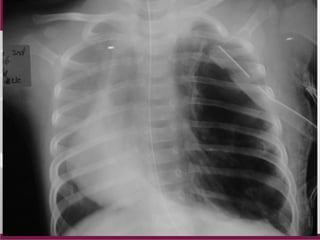

Respiratory Distress

• Day 1, Term 39 wks,

delivered in Sonepat

• Antenatal scan:

Polyhydramnios

• Respiratory distress

• Intubated and transferred

in BLK

A new born with

CONGENITAL DIAPHRAGMATIC HERNIA

Day 1

• Respiraory acidosis

(Ph 7.26/PO2 118/Pco2 47/Hco3 20.1)

• Assisted control ventilation

– Fio2 100%

– PIP/PEEP: 15/5

• Dopamine and Adrenaline (Mean 50mm Hg)

• Cardiac Echo: Mild Pulmonary Hypertension

Day 2

• One episode of desaturation

• Respiratory acidosis

• Shifted on HFO

MAP 14

Fio2 100%

Delta P 30

• Stable

Day 3

• Desaturated

• Rt Pneumothorax- Drained

Day 4(CDH Repair)